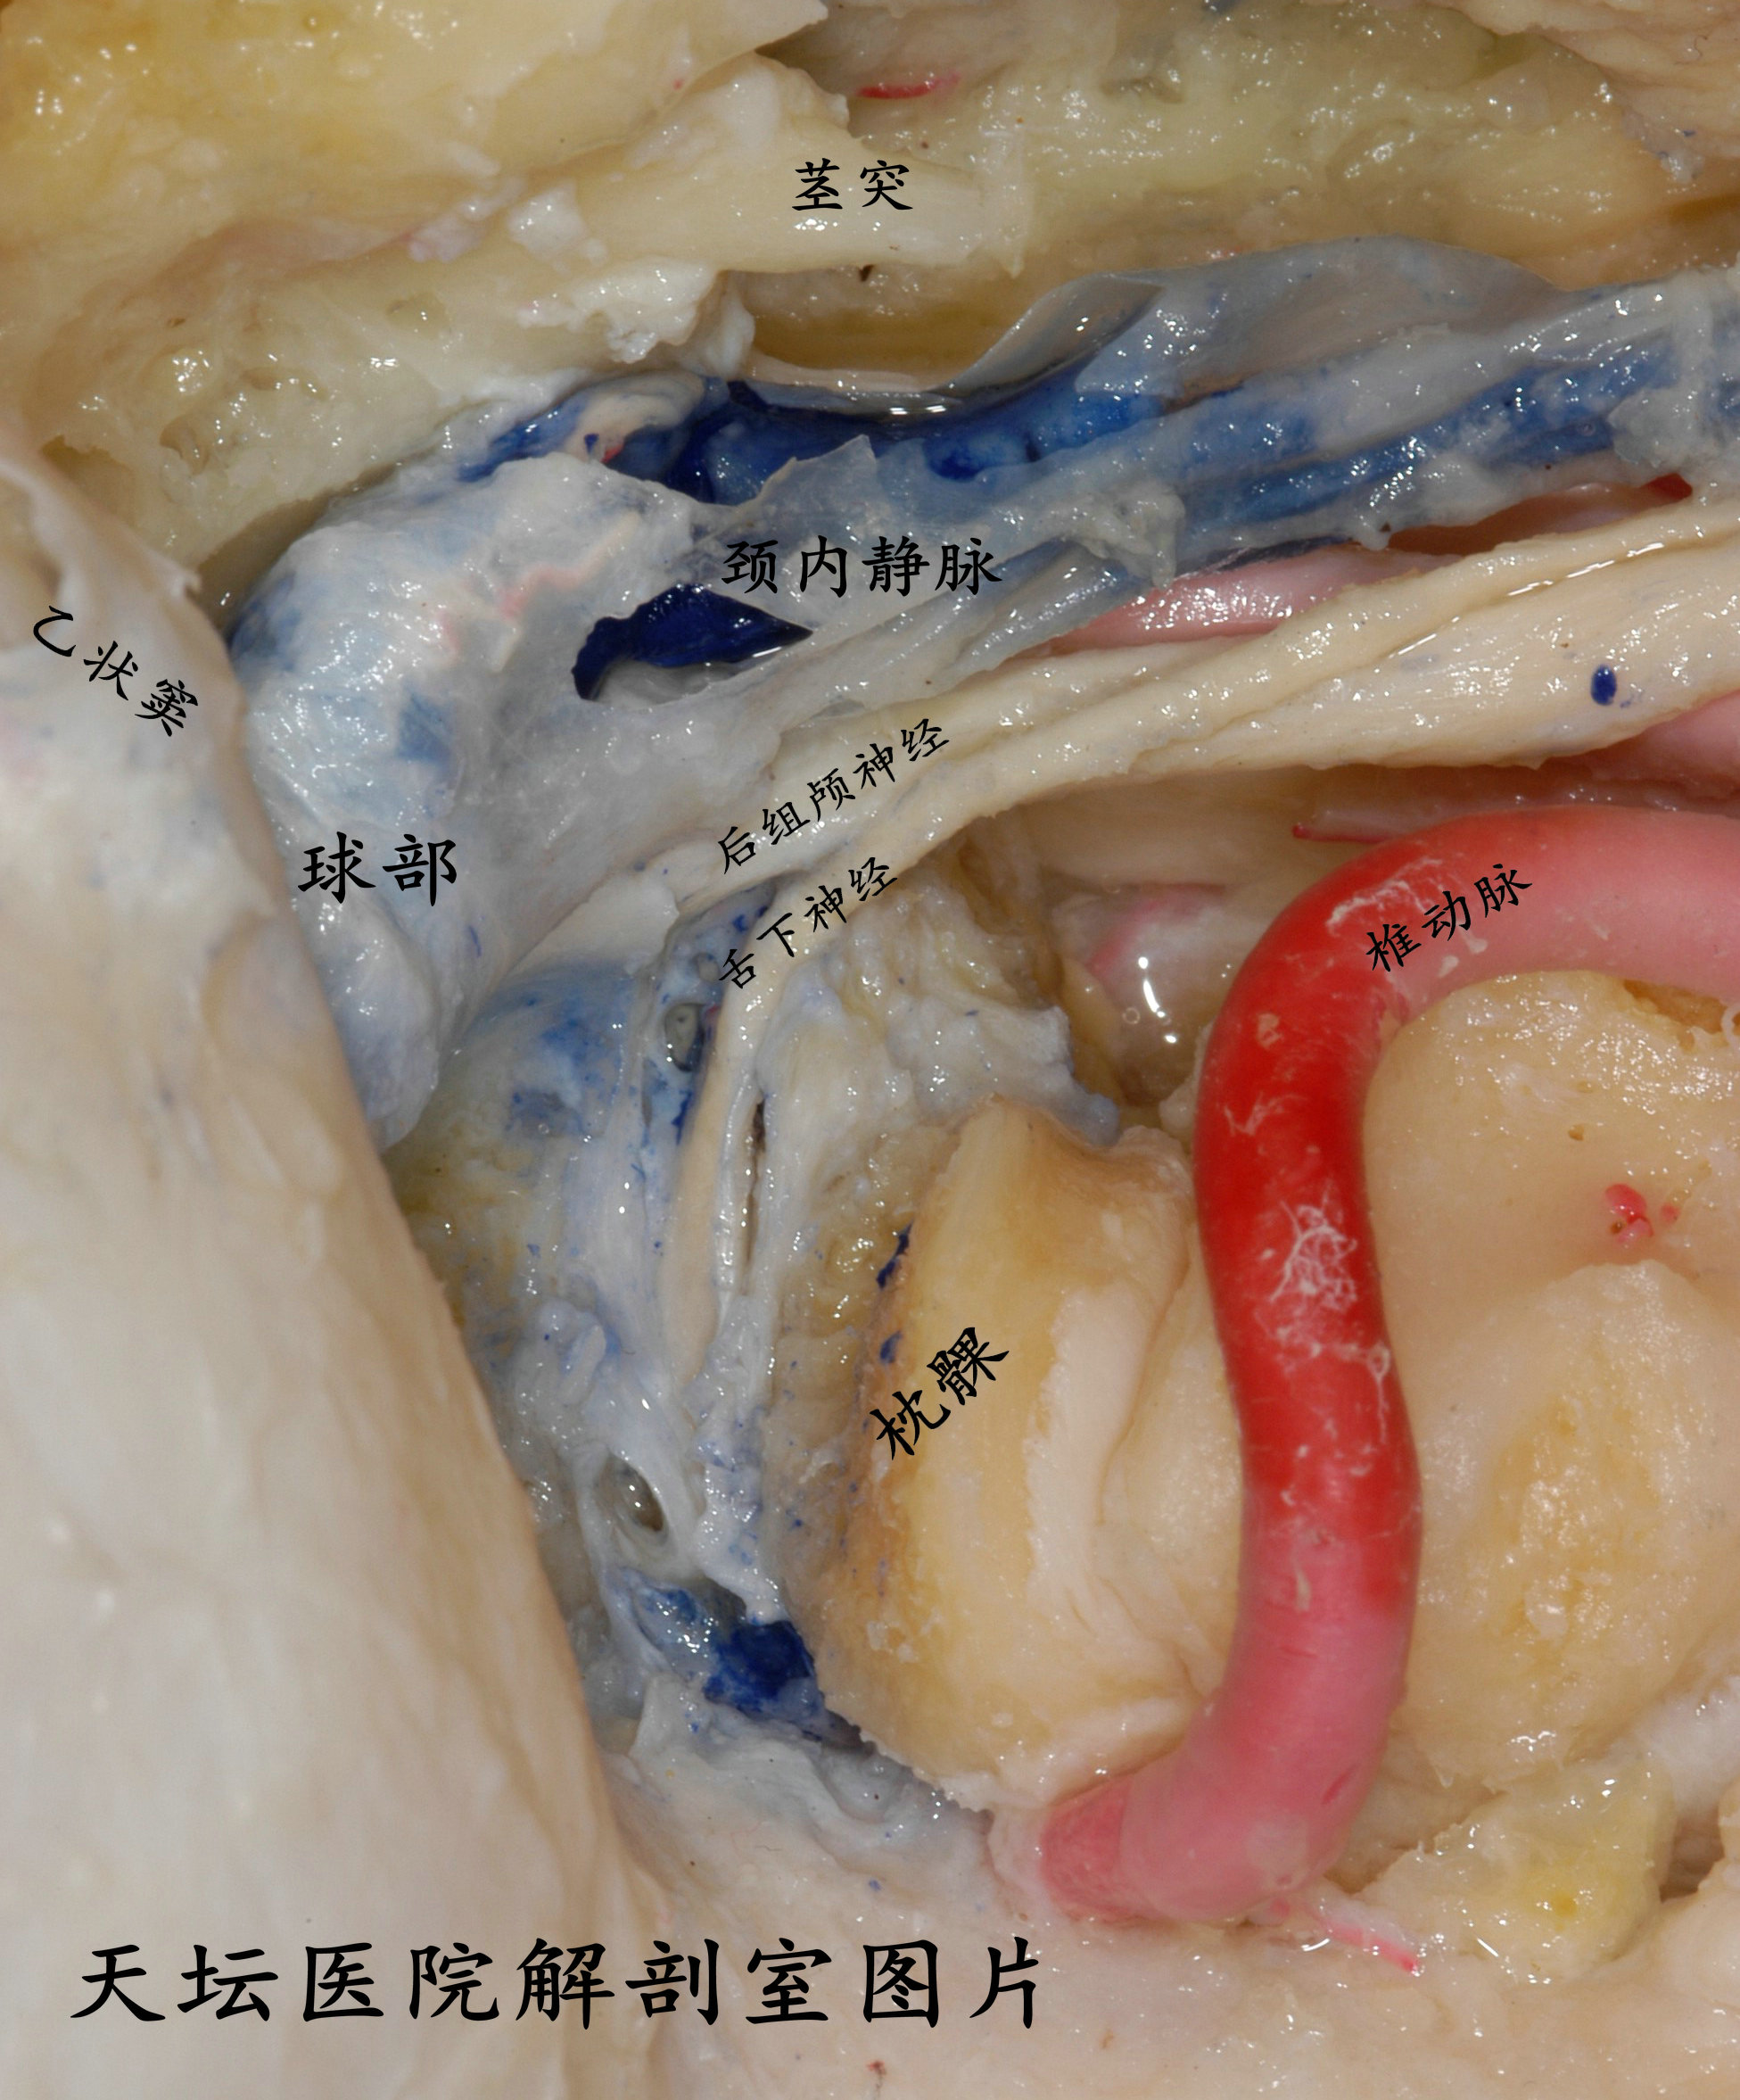

有时候会用椎动脉移位,对舌下神经管和颈静脉孔区暴露更好

因为颈静脉孔区毗邻舌下神经管区,所以远外侧髁旁入路和髁上入路都是用耳后C型切口。颈静脉孔区注重暴露颈静脉球部,舌下神经管区注重暴露枕髁。